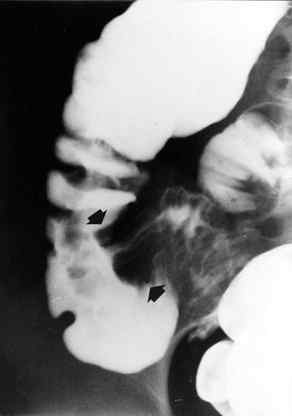

Dopo aver

allertato la Sala Operatoria, eseguiva clisma opaco (che conferma la

diagnosi)(Fig.3), per tentare la riduzione dell'invaginazione,

manovra che purtroppo non riesce. Alle ore 12 viene operata, con

riduzione del segmento invaginato, associato ad appendicectomia. E'

dimessa in 6° giornata perfettamente guarita.

Figura

3